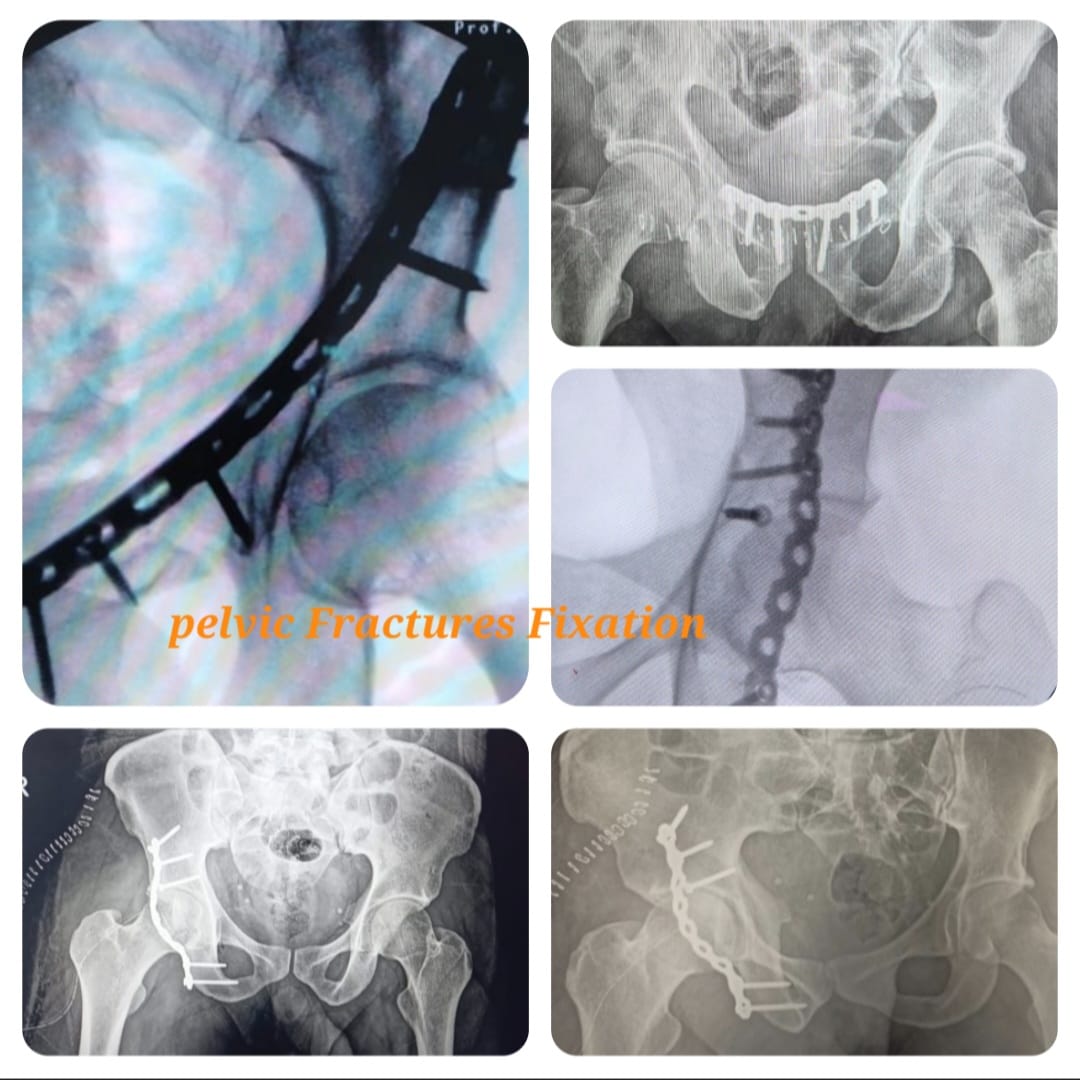

Pelvi acetabular surgeries are specialized orthopedic procedures performed to treat complex fractures and injuries involving the pelvis and acetabulum (hip socket). These injuries commonly occur due to high-impact trauma such as road traffic accidents, falls from height, or industrial injuries and require precise surgical intervention to restore pelvic stability and hip joint function.

Management of pelvic and acetabular fractures demands detailed preoperative planning using advanced imaging such as CT scans and three-dimensional reconstruction. Surgical fixation is performed using specialized plates and screws to accurately realign fractured bones, preserve joint congruity, and minimize long-term complications.